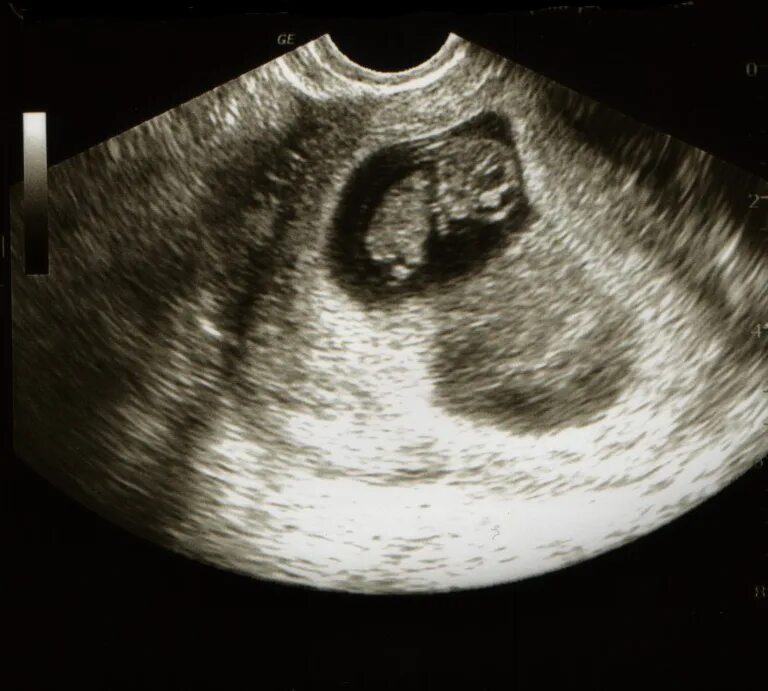

Работа на 9 неделе